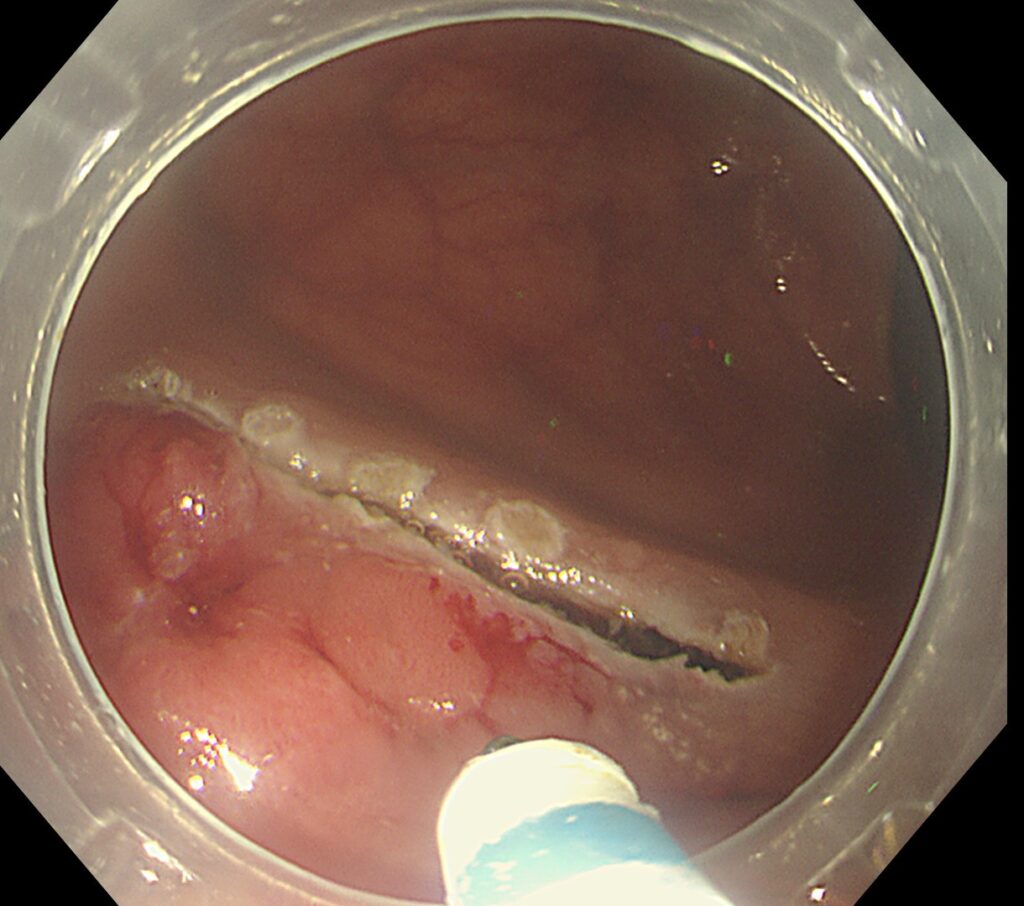

上図の如く、腫瘍辺縁にマーキングをおき、腫瘍サイズが大きいため、ポケット法による切除を選択しました。

腫瘍の遠位側に、メスをいれて、粘膜下層を充分トリミングします。

下が筋層、上が腫瘍です。遠位側の切開部位まで開通したら、両側を電気メスで外してあげると・・・